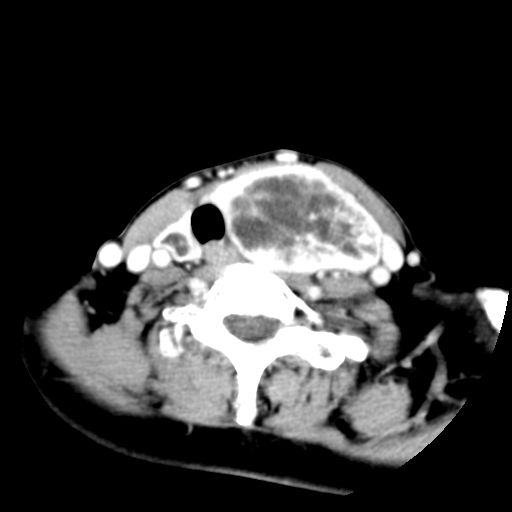

女  53岁  左侧甲状腺肿物3年,近2月明显增大。病理稍后发。

左侧甲状腺内见有一较大类圆形低密度区,边缘清楚光整,增强有一定强化,但仍较正常甲状腺组织强化弱,左侧甲状腺周围组织明显受压移位,且周围组织界限存在,周围组织间隙内未见肿大淋巴结,结合病史考虑为良性病变,左侧甲状腺腺瘤可能大。

左侧甲状腺内见有一较大类圆形低密度区,边缘清楚光整,增强有一定强化,但仍较正常甲状腺组织强化弱,左侧甲状腺周围组织明显受压移位,且周围组织界限存在,周围组织间隙内未见肿大淋巴结。

考虑:甲状腺囊腺瘤

双侧都有,最大病灶在左侧,其包膜和灶内部都有明显的强化,提示其血供丰富。我首先考虑是良性占位,以腺瘤可能性大。

左侧甲状腺内见有一类圆形低密度区,边缘清楚光整,可见明显增强,间隔亦可见增强,且与周围组织分解清晰,周围组织间隙内未见肿大淋巴结。右侧亦可见类似表现。考虑甲状腺腺瘤。

手术病理证实:双侧腺瘤样甲状腺肿。